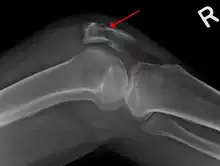

Osteochondral fracture of patella

Vertical patella fracture